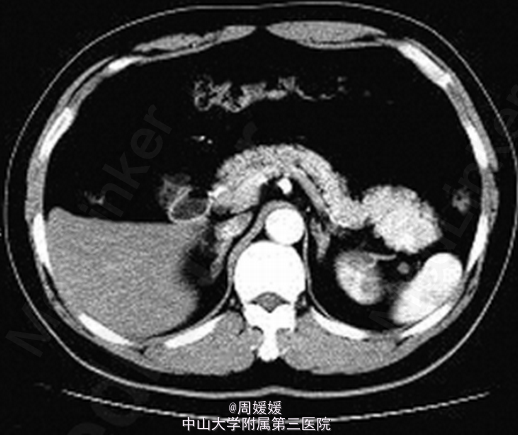

查体未见明显异常. 实验室检查:实验室检查 :肿瘤标志物甲胎蛋白 6.57ng/mL ,癌胚抗原3.64ng/mL ,糖类抗原1259U/mL ,糖链抗原19-9 12.30U/mL ,鳞状细胞癌相关抗原0.8ng/mL 。 B超提示:胰尾部可见一大小3.5cm*2.8cm 低回声区 ,边界尚清 ,内部回声不均。胰管不扩张。 增强CT提示:胰腺尾部可见一肿块影 ,大小约4.4cm*3.4cm*2.4 cm,动脉期、静脉期明显强化

术后病理:送检组织镜下见为基本正常的胰腺组织 ,部分包裹脾脏组织 ,脾小体结构清楚 。符合(胰体尾)副脾。 本例分析误诊原因主要 :1.副脾发生在胰腺尾部,与胰腺关系紧密,CT 横断面不分辨其来源,造成误诊;2.胰腺异位副脾,临床非常少见,部分影像科医师主观上对副脾的认识不足,尤其不清楚副脾 CT 影像学特点,看见胰腺尾部富血供肿瘤,首先考虑胰腺神经内分泌肿瘤、囊腺瘤(癌),实性假乳头状瘤,而造成临床误诊。